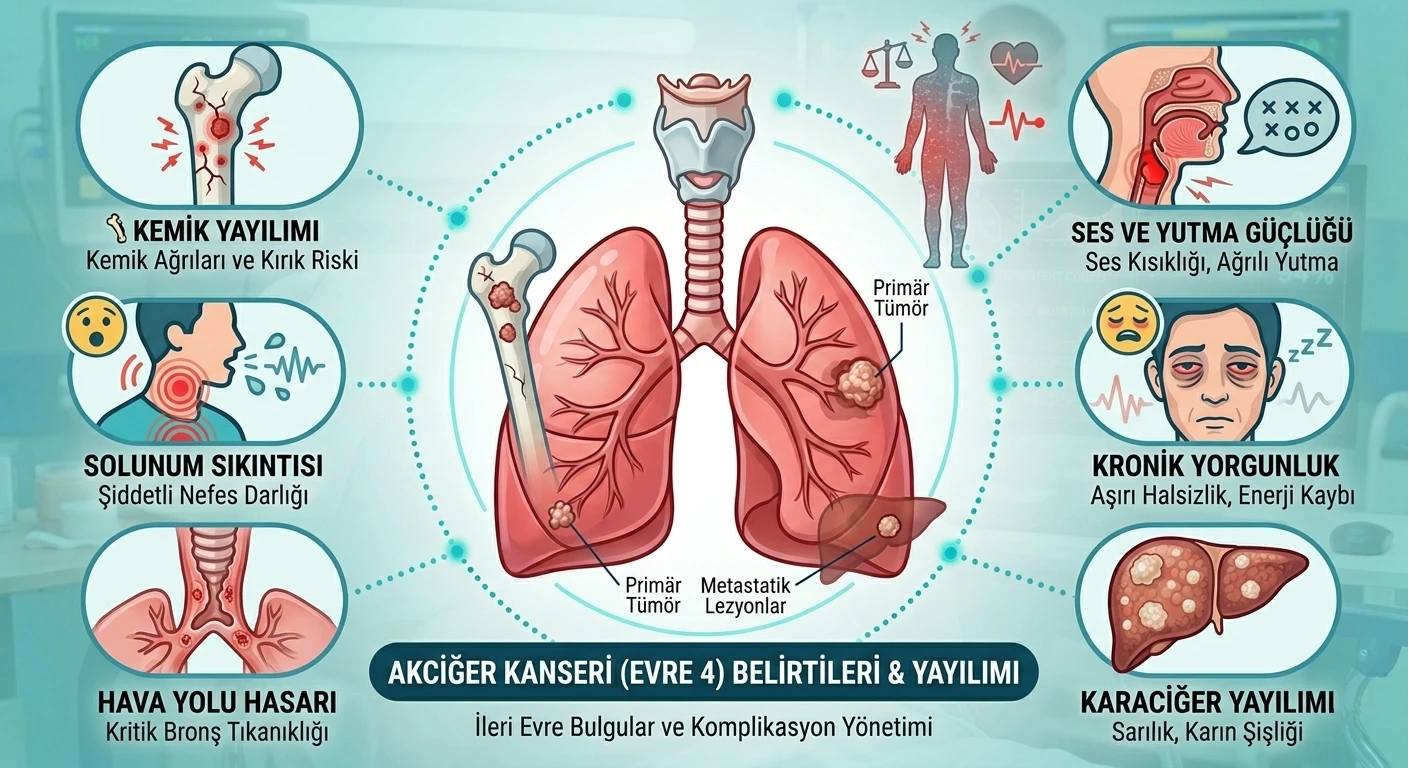

EVRE 4

EVRE 4

Kanser diğer organlara veya karşı akciğere sıçramıştır.